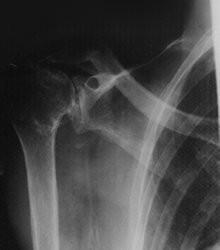

Se reconocen cinco síndromes : 1- Síndrome de la Costilla Cervical Supernumeraria. (Vesalio y Galeno). 2- Síndrome del Escaleno Anterior. (Naffiger 1937 ). 3- Síndrome Costoclavicular. (Falconer y Weddell 1943). 4- Síndrome de Hiperabducción del brazo. (Wright 1945). 5- Síndrome del Pinzamiento Neurovascular.

Síndrome de la Costilla Cervical

Supernumeraria:

• La presencia de la costilla cervical supernumeraria reduce el espacio interes-calénico y mantiene en posición forzada la arteria subclavia y el plexo braquial. fig # 3 Se hace el diagnóstico por palpación de la zona supraclavicular, estudio radiológico de la columna cervical, la presencia de un soplo sistólico producido por la compresión de la arteria subclavia y con frecuencia encontramos un aneurisma post-estenótico de la arteria subclavia. fig # 3

SINTOMAS… • Síntomas: En estos síndromes la sintomatología es local y similar para todos con algunas particularidades ya descrita en cada uno de ellos y se dividen en neurológicos y vasculares (venosos y arteriales). Diagnóstico por exámenes complementarios: " Rayos X simples de columna cervical anteroposterior, lateral y oblicua • Flujometría Doppler y Pletismografía digital • Electromiografía, velocidad de conducción nerviosa y potenciales evocados somatosensoriales de los miembros superiores en posición normal y dinámica